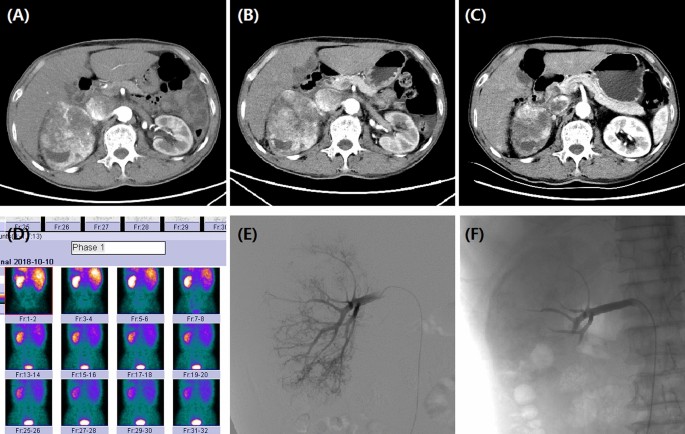

A 72-year male with right RCC treated by CB. (A) CT preoperative examination revealed a large tumor of the right kidney with tumor invasion into inferior vena cava. (B) The right renal tumor maintained stable after one month's follow-up. (C) The tumor shrunk at 3 months after DEB-TACE. (D) The right kidney showed a lower GFR (43.7 ml/min) than the left kidney (60.1 ml/min). (E) The right renal artery was the blood supply artery of the tumor. (F) The right renal artery was incubated and embolized.

We retrospectively collected baseline data such as demographic data, clinical data, illness history, complications, tumor size, tumor markers, white blood cell count, computed tomography (CT) imaging ( Fig. 1B,C; Fig. 4A–C) or MRI (Fig. 2), and so on (Fig. 4D).